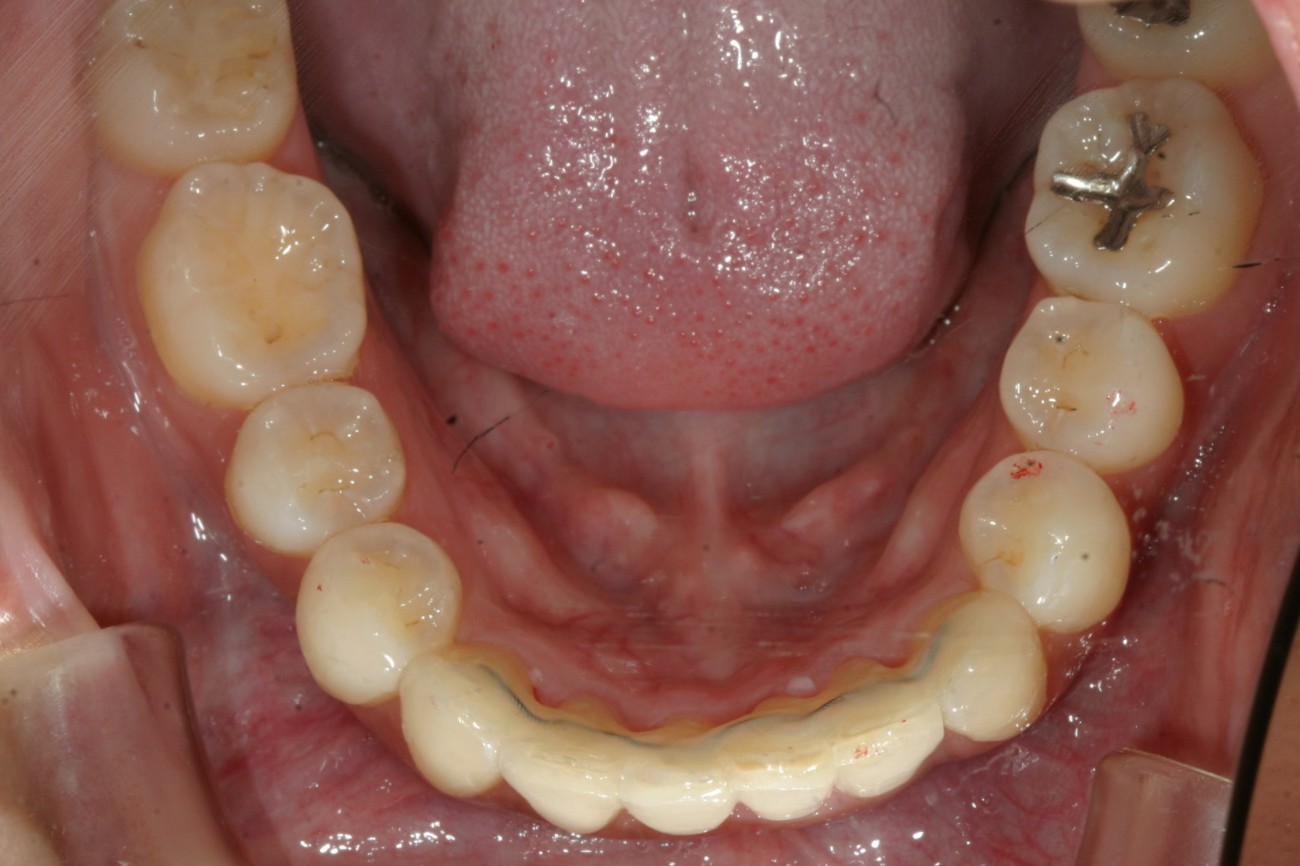

下顎もかなりの叢生です。

下顎もアーチを拡大する事でここまで綺麗に改善しました。